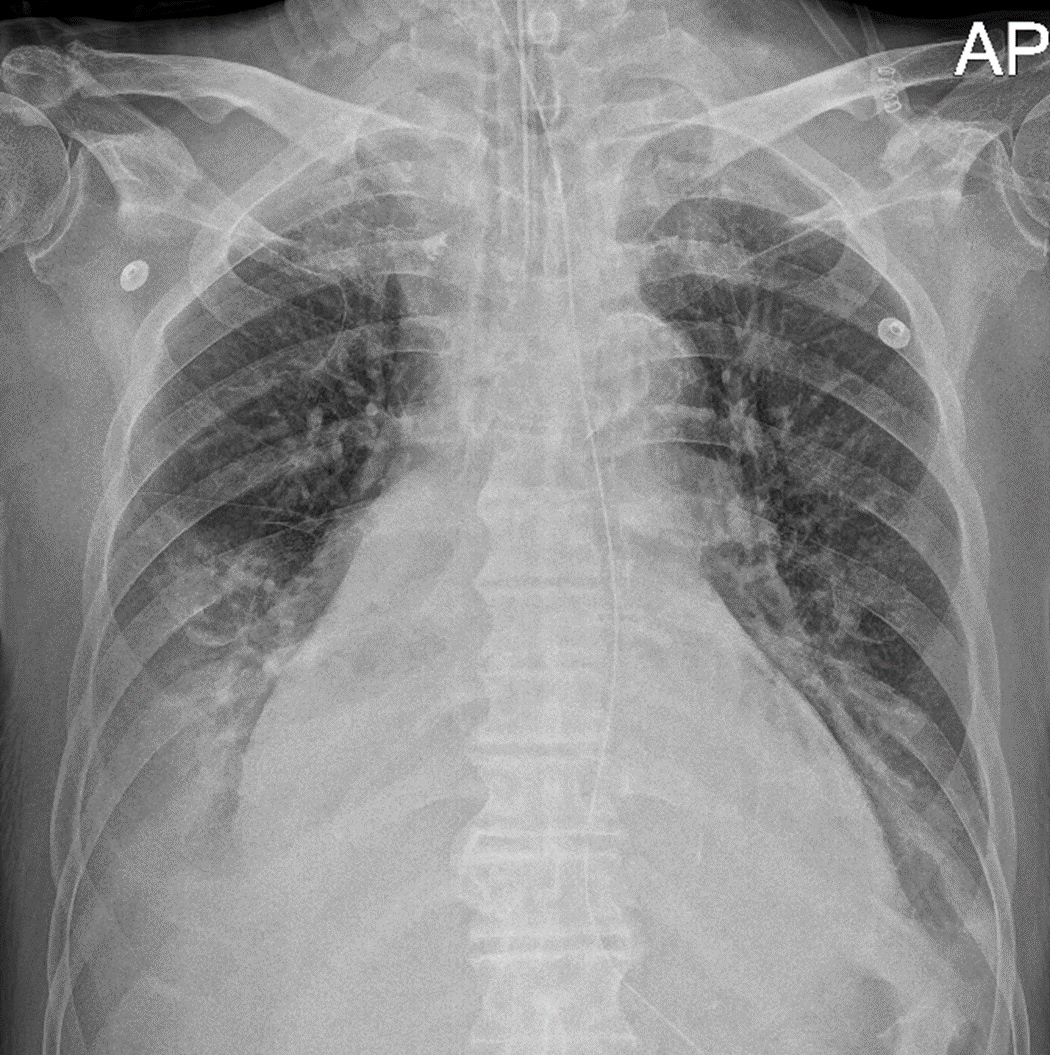

Pleural effusion이 환자의 증상에 영향을 미치는지 평가하는 것은 쉽지 않다. 일반적인 증상으로 dyspnea, chest pain, cough가 있을 수 있다. 이전에 배액술을 시행한 적이 없는 환자에서 pleural effusion이 증상을 유발했는지 여부는 고민이 필요하다. 많은 경우에서 증상의 정도와 effusion의 estimated size는 판단에 도움을 줄 수 있다. 예를 들어 acute heart faliure(급성 심부전) 환자에서 발생한 small- to moderate-sized pleural effusion은 이뇨제에 반응하고 증상이 호전된다면 배액이 필요하지 않다.

반면에 pneumonia로 인해 상당한 dyspnea와 많은 양의 pleural effusion을 보이는 환자에서는 배액을 해야 한다. 배액의 적응증에 해당되는 경우라면 가능한 한 빨리 시행해야 하는데 상태 확인 후 12시간에서 24시간 이내에는 시술을 해야 한다. 특히 pleural space가 감염된 환자(eg, complicated parapneumonic effusion, tuberculous pleuritis, empyema)나 배액을 하지 않을 시 intubation(기관 내 삽관)이나 mechanicl ventilation(기계 호흡)이 필요할 정도로 심한 증상을 보이는 환자에서는

더욱 그렇다.